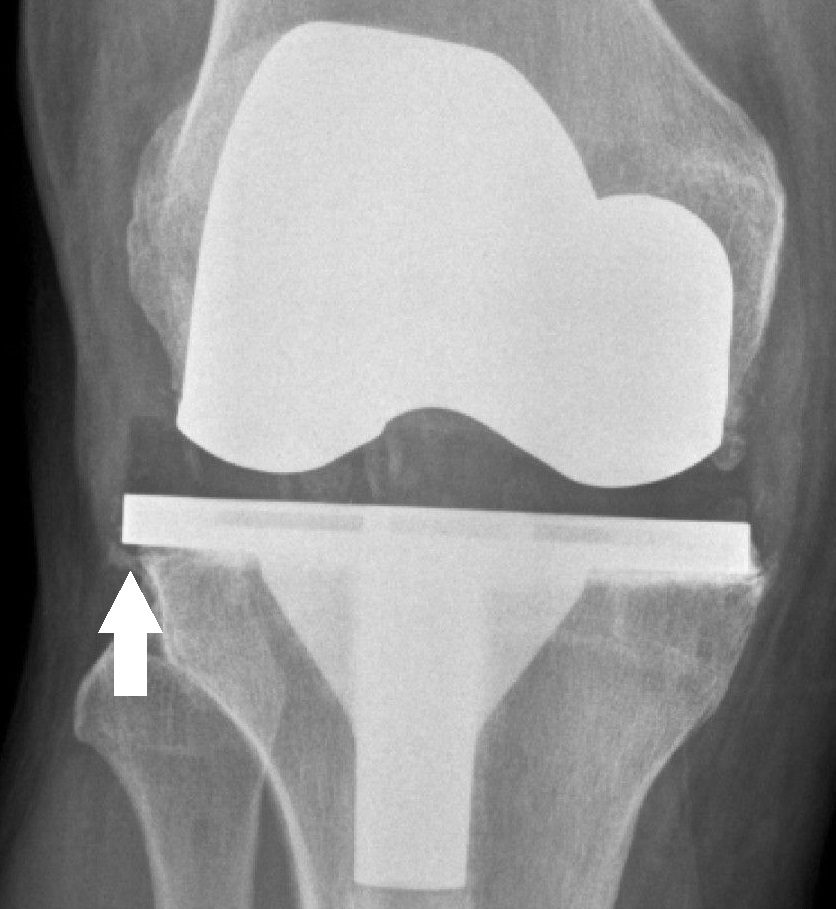

Annotated X-ray of a knee prosthesis showing component overhang after total knee arthroplasty.